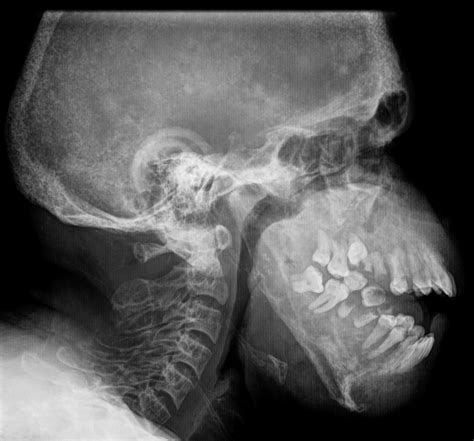

El hueso es el principal reservorio de calcio y fósforo en el organismo. Aproximadamente el 99% del calcio corporal y cerca del 80% del fósforo se localizan en el esqueleto.

Tres tipos principales de células intervienen en la formación y resorción ósea:

- Osteoblastos: Sintetizan colágeno y promueven el depósito de sales cálcicas, participando activamente en la formación ósea.

- Osteoclastos: Son responsables de la resorción del hueso, descomponiendo la matriz ósea a través de enzimas lisosomales y fagocitosis.

- Osteocitos: Derivados de los osteoblastos, una vez rodeados por matriz calcificada, son las células más numerosas. Juegan un papel fundamental en el intercambio de calcio entre el líquido extracelular y el hueso, una función regulada hormonalmente.